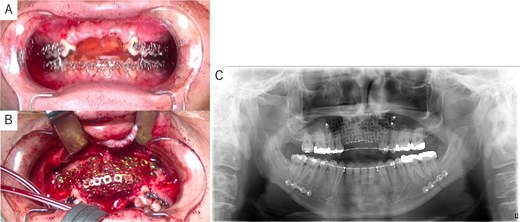

Simulation of dental implant placement in the maxillary anterior region using coDiagnostiX® (Straumann, Basel, Switzerland) revealed insufficient bone volume in both height and width (Fig. 3A). A 3D simulation was performed for bone augmentation in the maxillary anterior region alongside posterior mandibular movement. Mandibular retraction measured 6.2 mm on the right side and 7.0 mm on the left side. DICOM files from dental cone-beam computed tomography were converted to Standard Tesselation Language (STL) data using Volume Extractor® (Volume Extractor 3.0; i-Plants Systems Corporation, Iwate, Japan) (Fig. 3B). Osteotomy lines and the required bone augmentation were established using Geomagic Freeform® (3D Systems, Rock Hill, SC, USA) (Fig. 3C). A 3D model was printed (Straumann® CARES® P20+; Straumann, Basel, Switzerland) from the STL data, and a titanium mesh (Universal Mesh; Stryker Japan, Tokyo, Japan) was shaped to maintain space for PCBM grafting (Fig. 3D). The planned augmentation volume for implant placement was 5.6 mL, with a target bone harvest volume of 9 g, sourced from the right anterior iliac crest. In October 2023, SSRO and bone augmentation were performed simultaneously as planned (Fig. 4A). After harvesting PCBM from the right anterior iliac crest, SSRO was completed. The harvested PCBM was grafted into the bone defect and secured with the pre-bent titanium mesh (Fig. 4B). The wound was sutured, concluding the first operation.

Intraoperative and postoperative images. (A) SSRO surgery was performed with conformity to the orthodontist-prepared final splint. (B) PCBM was grafted into the bone defect and covered with titanium mesh. (C) Postoperative panoramic radiograph showed no abnormalities.